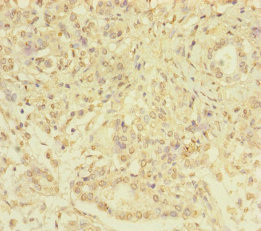

Immunohistochemistry of paraffin-embedded human pancreatic cancer using CSB-PA021074ESR1HU at dilution of 1:100